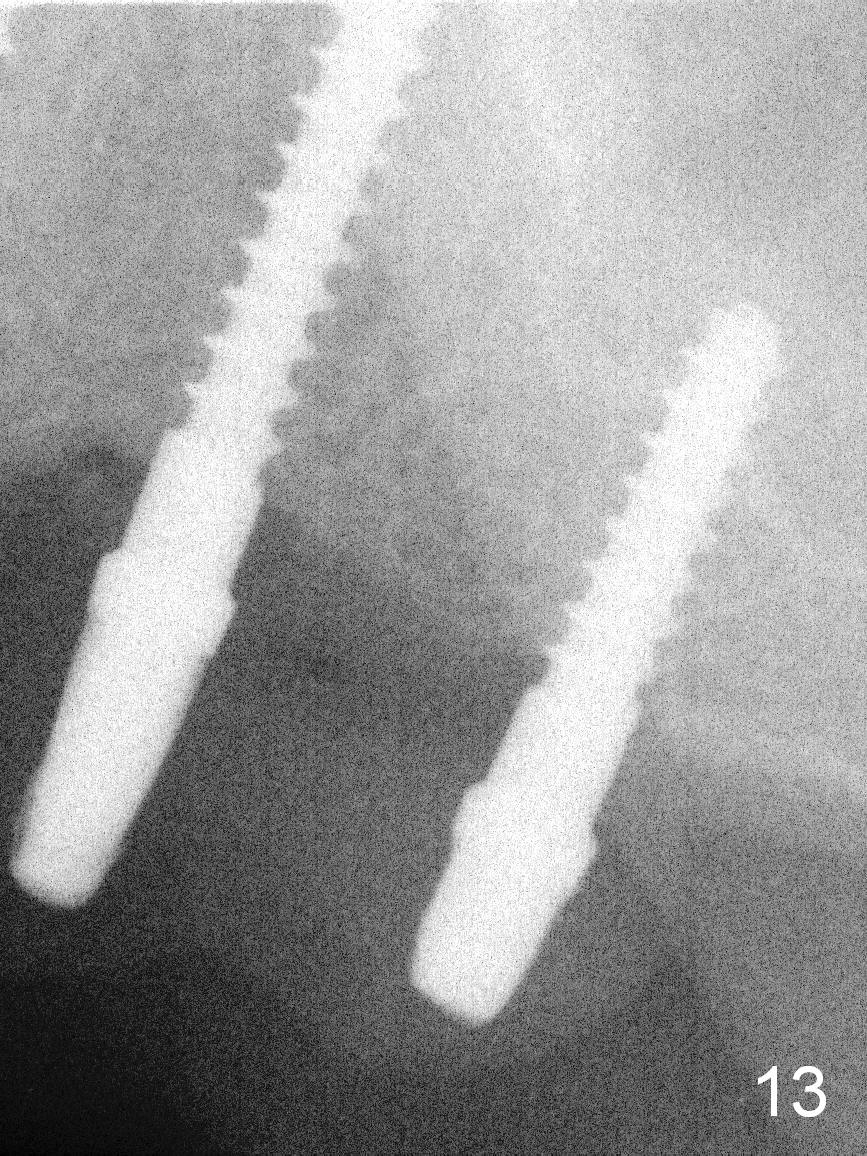

When the patient returns for implant placement (2nd visit after initial exam), he reveals that he is a dental phobic.  He requests placement of 4 implants in the upper left quadrant, instead of 2.  Narrow ridge is unexpected in the canine and premolar area (Fig.1).  Limited bone height at #13 (Fig.3 arrowheads: sinus floor) is found when initial drills are in place (Fig.2,3).  A 2-piece implant (4.5x17 mm tissue-level) is placed at #10 after extraction, while 1-piece implants are placed at 11 (3x17 mm (tissue-level, 15 °) and 12 and 13 (bone-level, 2.5x14, 12 mm, respectively; Fig.4,5).  In fact the 1 piece implant at #13 is not completely placed (Fig.5).  It is removed, the apical 3 threads are cut off (Fig.6 <, since a shorter implant was unavailable in the office) and the remaining implant is re-inserted.  The insertion torques of the 4 implants are ~ 60, ~ 35, < 35 and 15 Ncm, respectively.  After adjustment (Fig.7), immediate provisionals are fabricated at #10 and 11 (Fig.8, later splinted with composite), while perio dressing is applied around the implants at #12 and 13 and the provisionals at #10 and 11.  There is no nasal hemorrhage postop.  Although the perio dressing is loose 1 week postop (Fig.9), it is not removed.  When the upper lip fissure (Fig.9 <) heals, provisionals at #12 and 13 are planned to be splinted to the other two ones.  Two weeks postop, the upper lip fissure heals, the perio dressing dislodges and the implants at #12 and 13 are stable (Fig.10).  After abutment height adjustment, a splinted provisional is fabricated over these 2.5 mm 1-piece implants (Fig.11).